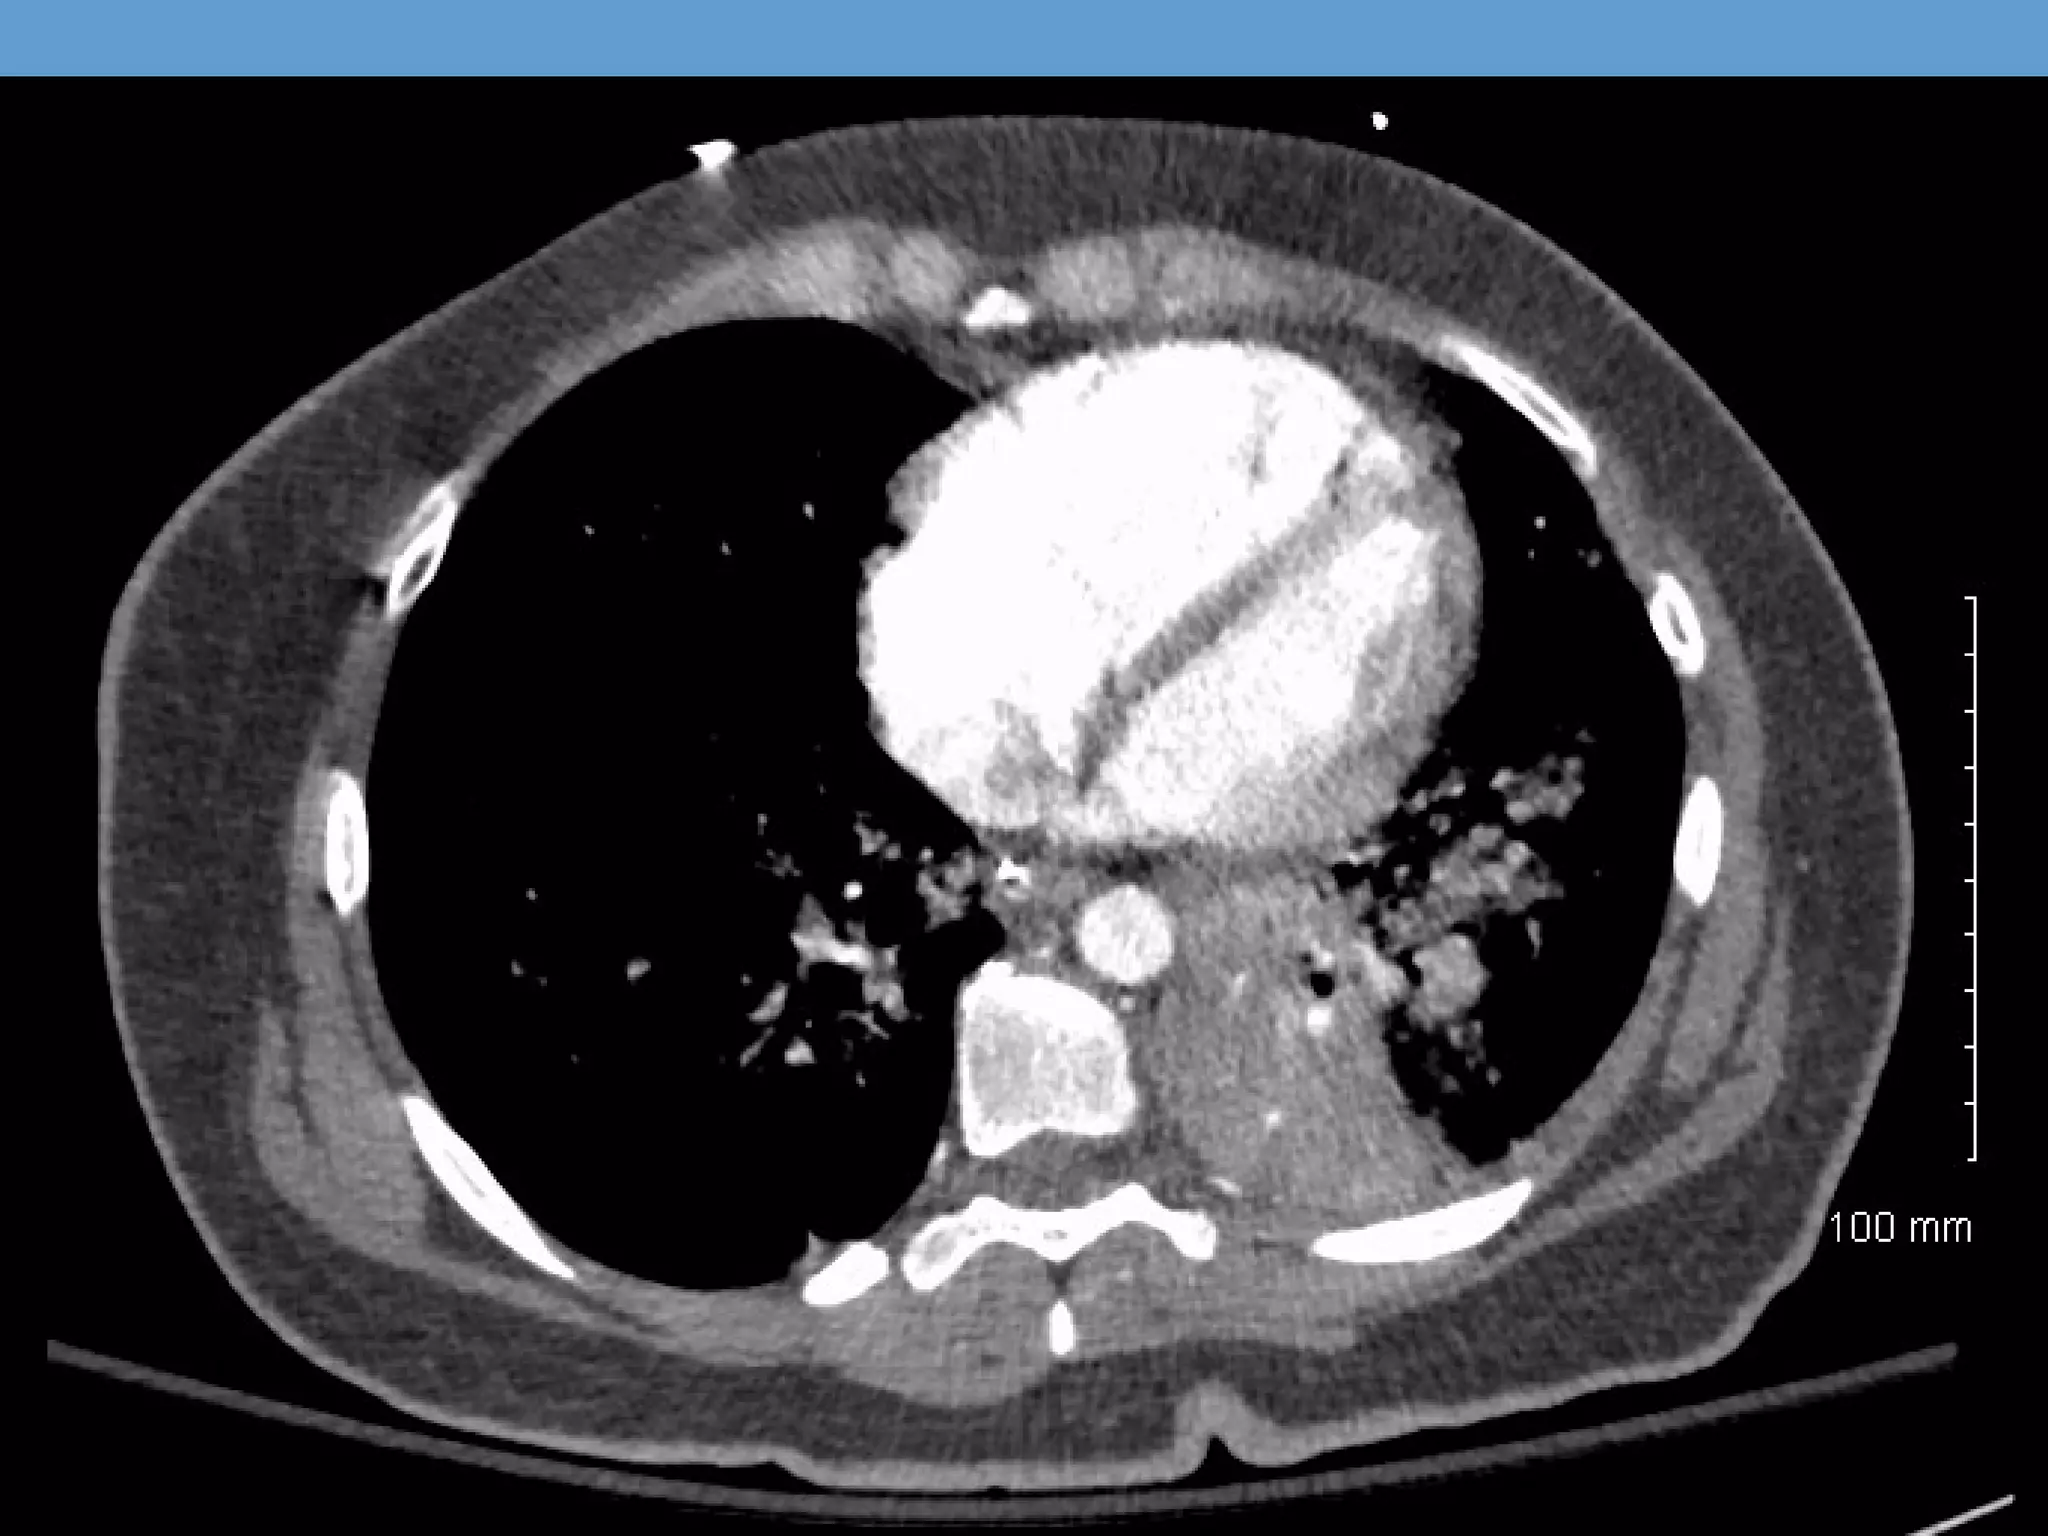

Our patient

• Repeat CT showed migration of thrombus

CT PE Protocol CTCHEST W CONTRAST (PE) PROTOCOL 11/1/2013 1:01 PM Findings: Opacification of the pulmonary vasculature is good. There is a saddle embolus with clot extending predominantly into the lower lobe pulmonary arteries, with the most significant clot burden in the left lower lung. Additional regions of emboli are seen in the right middle lobe There is evidence of right heart strain with a right ventricle to left ventricular ratio of greater than 1.

Our patient • tPAwas administered with little to no benefit at four hours • Surgical thrombectomy not available at FAHC • Urgently transferred by air to Brigham and Womens • Repeat CT showed migration of thrombus • Supportive care continued in MICU